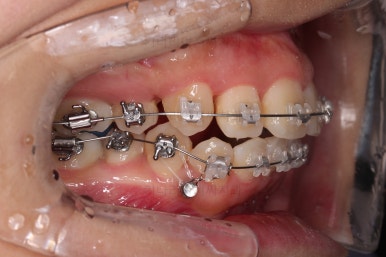

장치를 부착합니다.

이번 환자분이 선택한 장치는 엠파워 클리어라고 하는 자가결찰 세라믹 장치인데요.

철사를 묶는(결찰) cap이 장치에(자가) 달려있는 장치 중에 세라믹 성분으로 되어 심미성이 우수한 브라켓입니다.

대표적으로는 클리피씨 장치 등이 있습니다.

우선은 적응을 위해서 윗니만 장치를 부착하고요.

아랫니는 과개교합 개선을 위해 앞니 먼저 시작합니다.

아래 앞니는 깊숙하게 솟구쳐 오른 치아를 밑으로 끌어내리기 위해 미니스크류를 식립하게 됩니다.